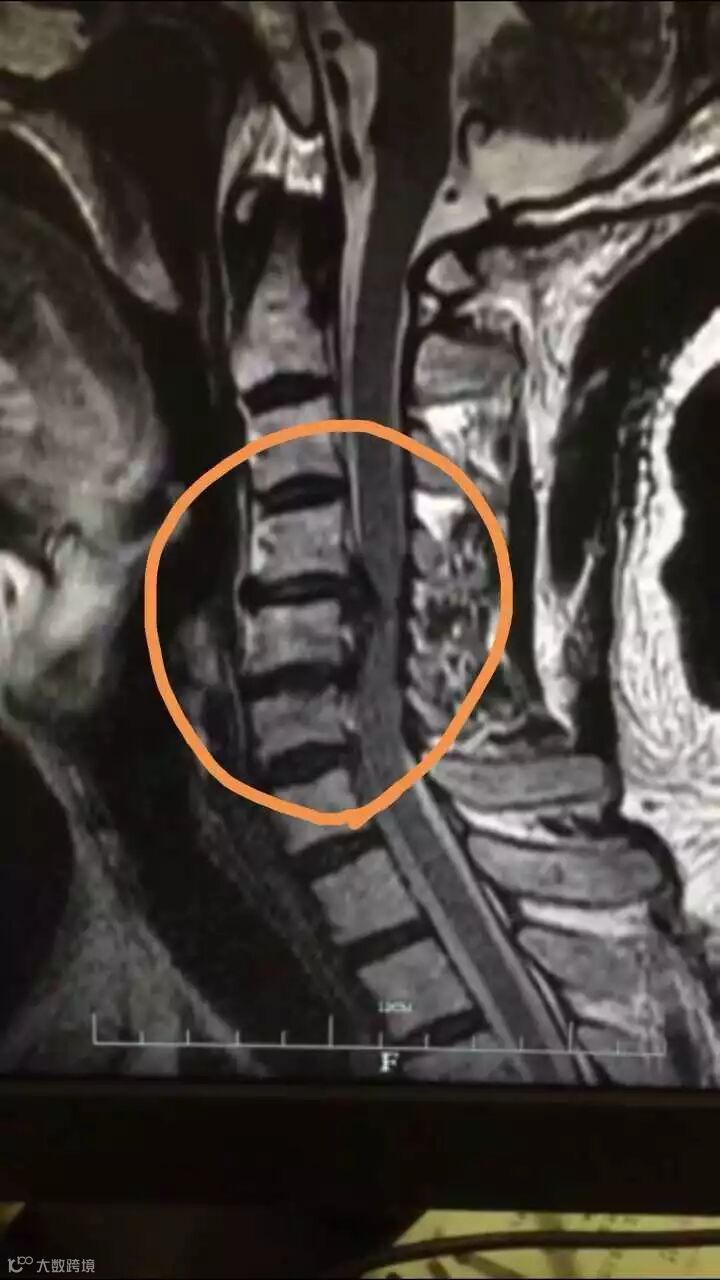

李先生被紧急送医,确诊为C4-5和C5-6椎间盘突出、相应椎管狭窄及脊髓变性,随后立即接受手术。时间若再晚一点,人很可能会瘫痪。

浙江大学医学院附属邵逸夫医院骨科副主任赵凤东主任医师说,患者发病与他坐火车睡觉时,长时间保持同一个姿势有关。在这个过程中,颈椎脊髓受到了严重压迫。

“检查发现,他的颈椎脊髓从椭圆形被压迫成月牙形,以至于影响到脊柱神经功能,小便无法解出,人处于不完全瘫痪状态。而在颈椎病突发患者中,因为坐火车导致发病如此之重的,这是我们遇到的第一例。”